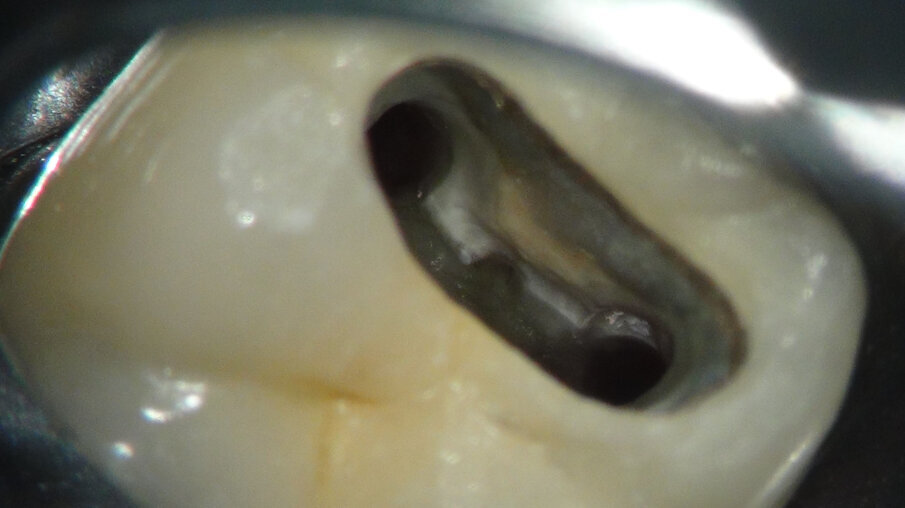

Na anesthesie en rubberdam maken we de access (afbeelding 8 en 9). De zwarte plastic Thermafil carriers zijn duidelijk te zien. Na wat gutta verwijderd te hebben, blijft er op de isthmus iets guttapercha achter. Zou ik dan toch vier jaar geleden een MidMesial gemist hebben (afbeelding 10)? We richten onze inspanningen eerst op de midmesial. Een uur later geef ik het op. Ik durf ook niet verder af te dalen in het relatief smalste deel van de mesiale radix. Het gevaar op een perforatie wordt me te groot (afbeelding 11 en 12).

Afbeelding 8. Na anesthesie en rubberdam maken we de access.